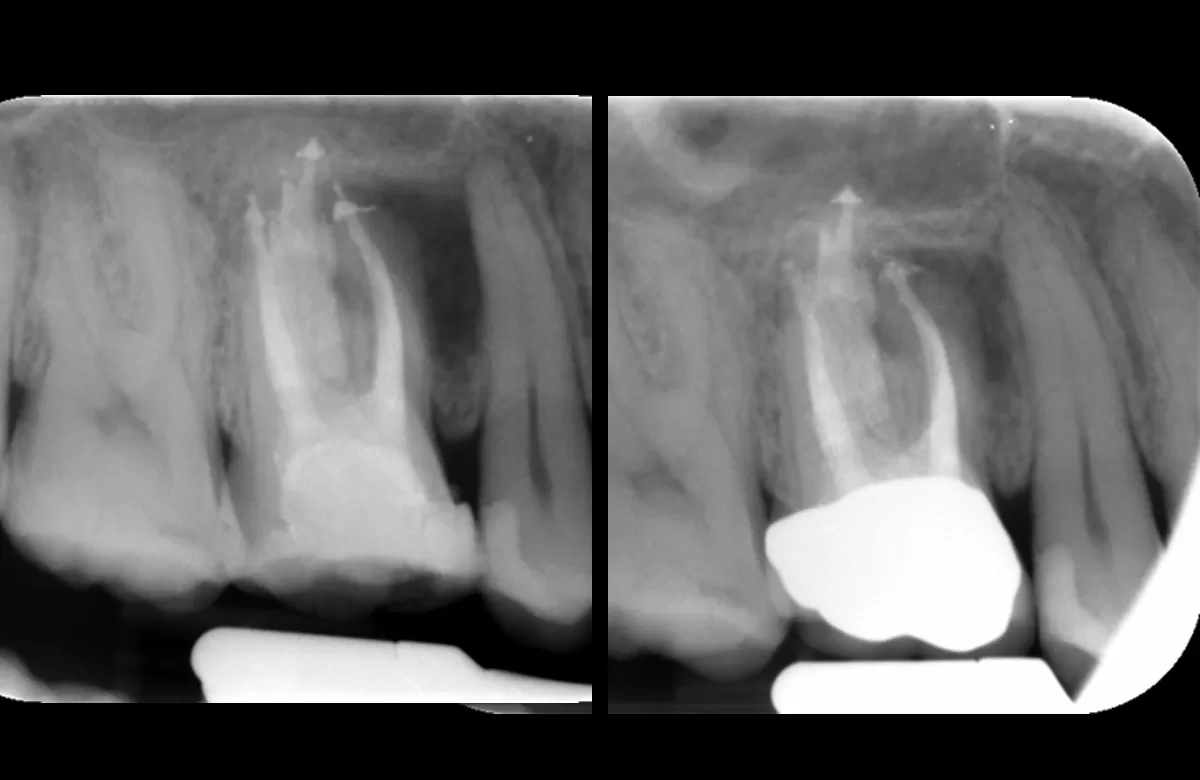

Pre obturation periapical radiograph of the tooth 16, checking cone length

Post obturation periapical radiograph showing obturation to length; right image: Review periapical radiograph showing increased bone infill around the mesiobuccal root

| PA demonstrates | Increased bone infill in comparison to post obturation PA taken 6 months prior |

| Obturation | With GP & AH Plus sealer. Warm vertical condensation technique. |

| Review | Healing in progress |